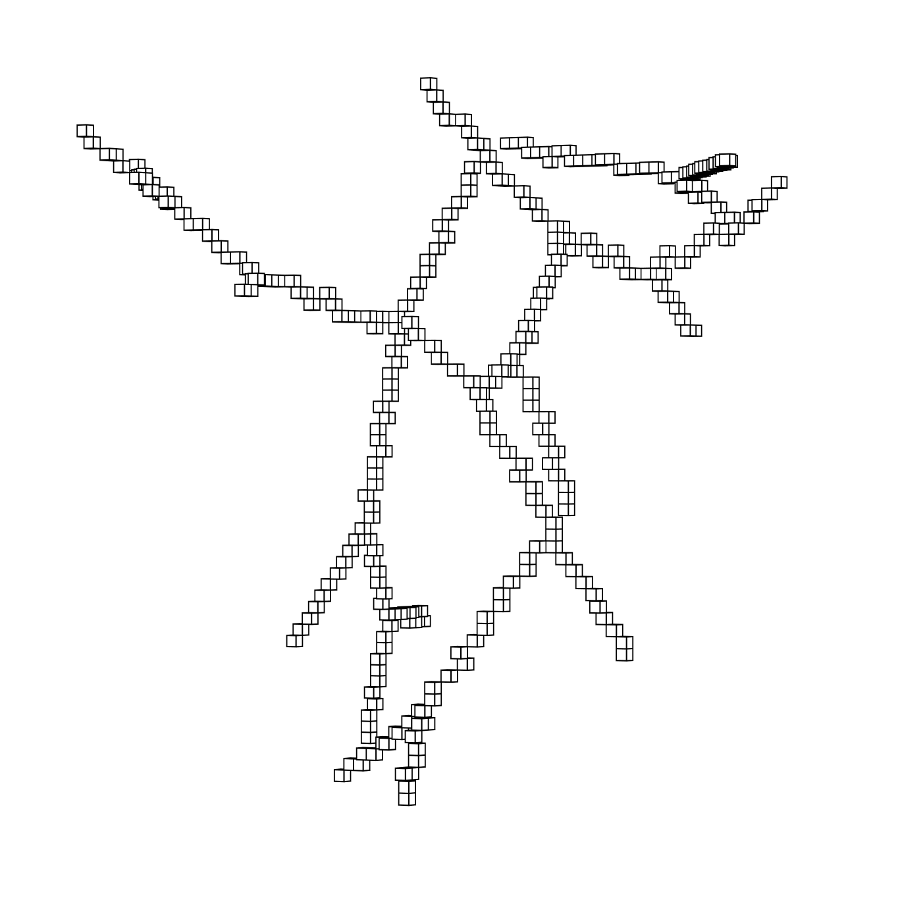

3.2 Connected Geodesic Paths as Vascular Tree

Representative examples of degraded synthetic images from SVT and the respective GT are shown in fig. 4 together with the connected graphs extracted by VTrails. Analogously, the same set of images are reported for the real images TOF and CTA in fig. 4. Qualitatively, the extracted set of connected geodesic paths shows remarkable matching with the provided GT in all cases. First, we verify the acyclic nature of the graph. We found no cycles, degenerate graphs and unconnected nodes, meaning that the extracted connected geodesic paths represent a connected geodesic tree. Precision and recall are then evaluated for the identified branches. Also, error distances are determined as the connected tree’s binary distance map evaluated at GT. Average errors () precision and recall are reported (meanSD) in table 1. Note that no pruning of any spurious branches is performed in the analysis.